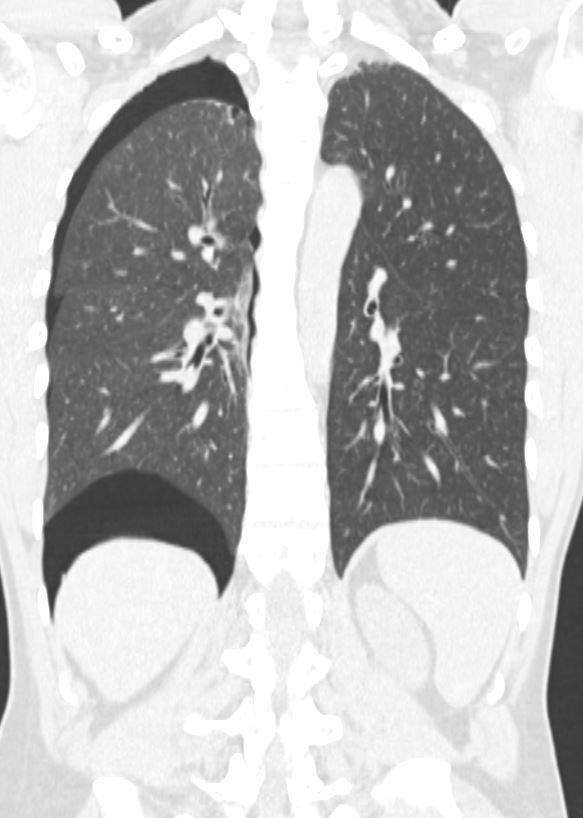

*27-year-old male with pleuritic chest pain and mild dyspnoea.

What is the most likely diagnosis?

Answer: Secondary spontaneous pneumothorax secondary to blebs